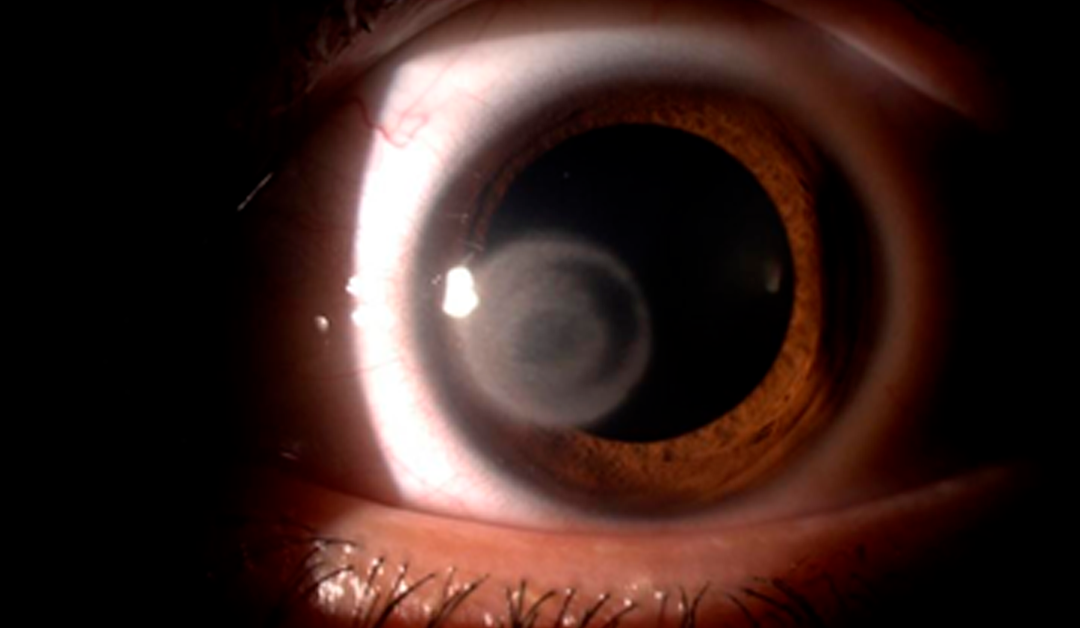

Queratitis por Acanthamoeba en LC híbridos: Una afección rara pero agresiva

Se ha señalado que el uso de lentes de contacto (LC) puede estar asociado a un mayor riesgo de queratitis microbiana. Este es un aspecto preocupante, ya que la falta de adherencia a las recomendaciones por parte de los pacientes es relativamente común. En este...